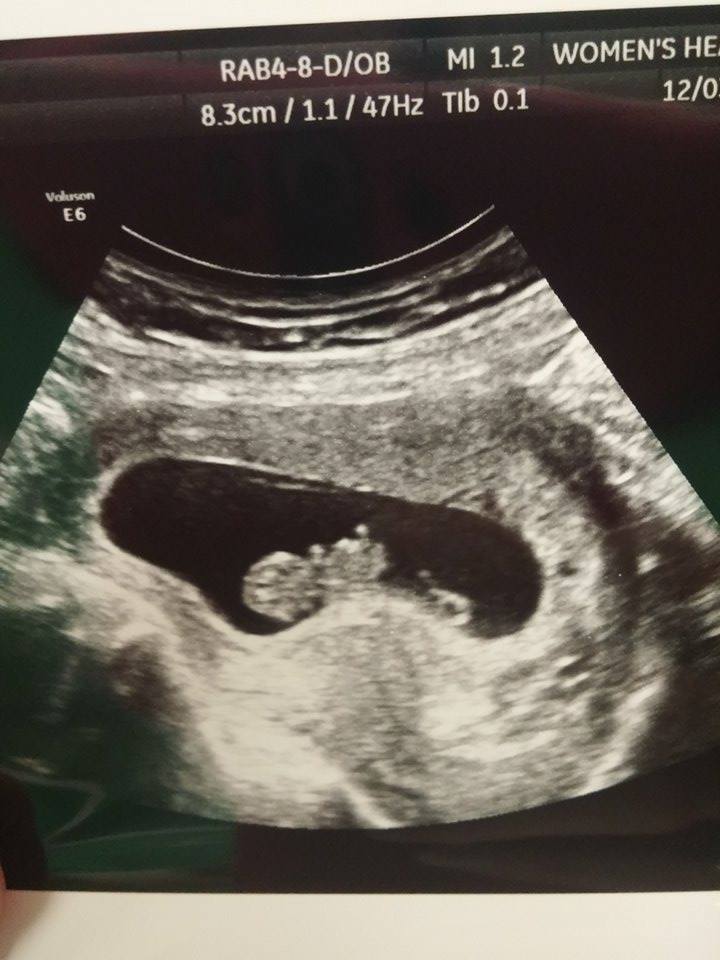

I had my second u/s on Tuesday at 8 weeks and 6 days. The baby is still measuring three days behind but they have not changed my edd. It was great to see how big the baby has gotten and to see its heart still beating. I go back on the 23 for some genetic testing and I get an u/s at that appointment, which was a great surprise to hear that. The equipment at the new place I have to go to is so much better than what my doctor has. Im hoping I can actually hear the heart beat at that appointment. I have not been able to hear it or to know how many bpm it is. But here is my little bean!

Btw I have no clue what those white lines are and neither does my doctor.